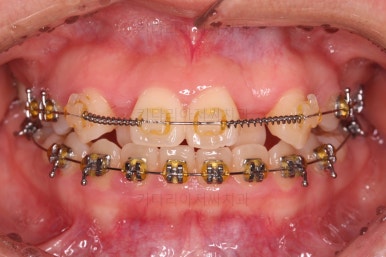

초진 때의 입안 모습입니다.

원래 다니던 치과에서 1년여 교정치료를 진행하신 상태였는데요.

몇 가지 이상한 점이 보이죠?

한 쪽만 발치가 되어있다.

아랫니에 유치가 2개가 그대로 남아있다.(화살표)

몇몇 이아에는 장치가 부착되어 있지 않다.

치과의사는 저마다의 스토리를 가지고 교정치료를 하기 때문에 나름의 논리와 방법으로 치료를 하셨겠지만 문제는 환자분이 느끼는 소통의 부재, 신뢰 상실 등이었어요.